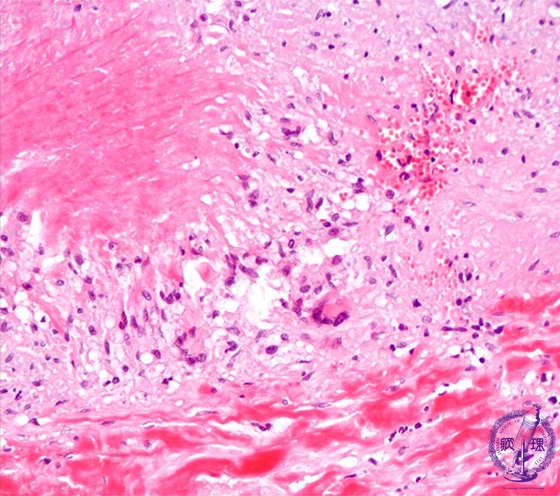

- (13)Takayasu arteritis

Microscopic image (HE, high power view): There is necrotizing, granulomatous inflammation composed of a Langhans giant cell infiltrate and central necrosis at the rupture site of the elastic lamellae.